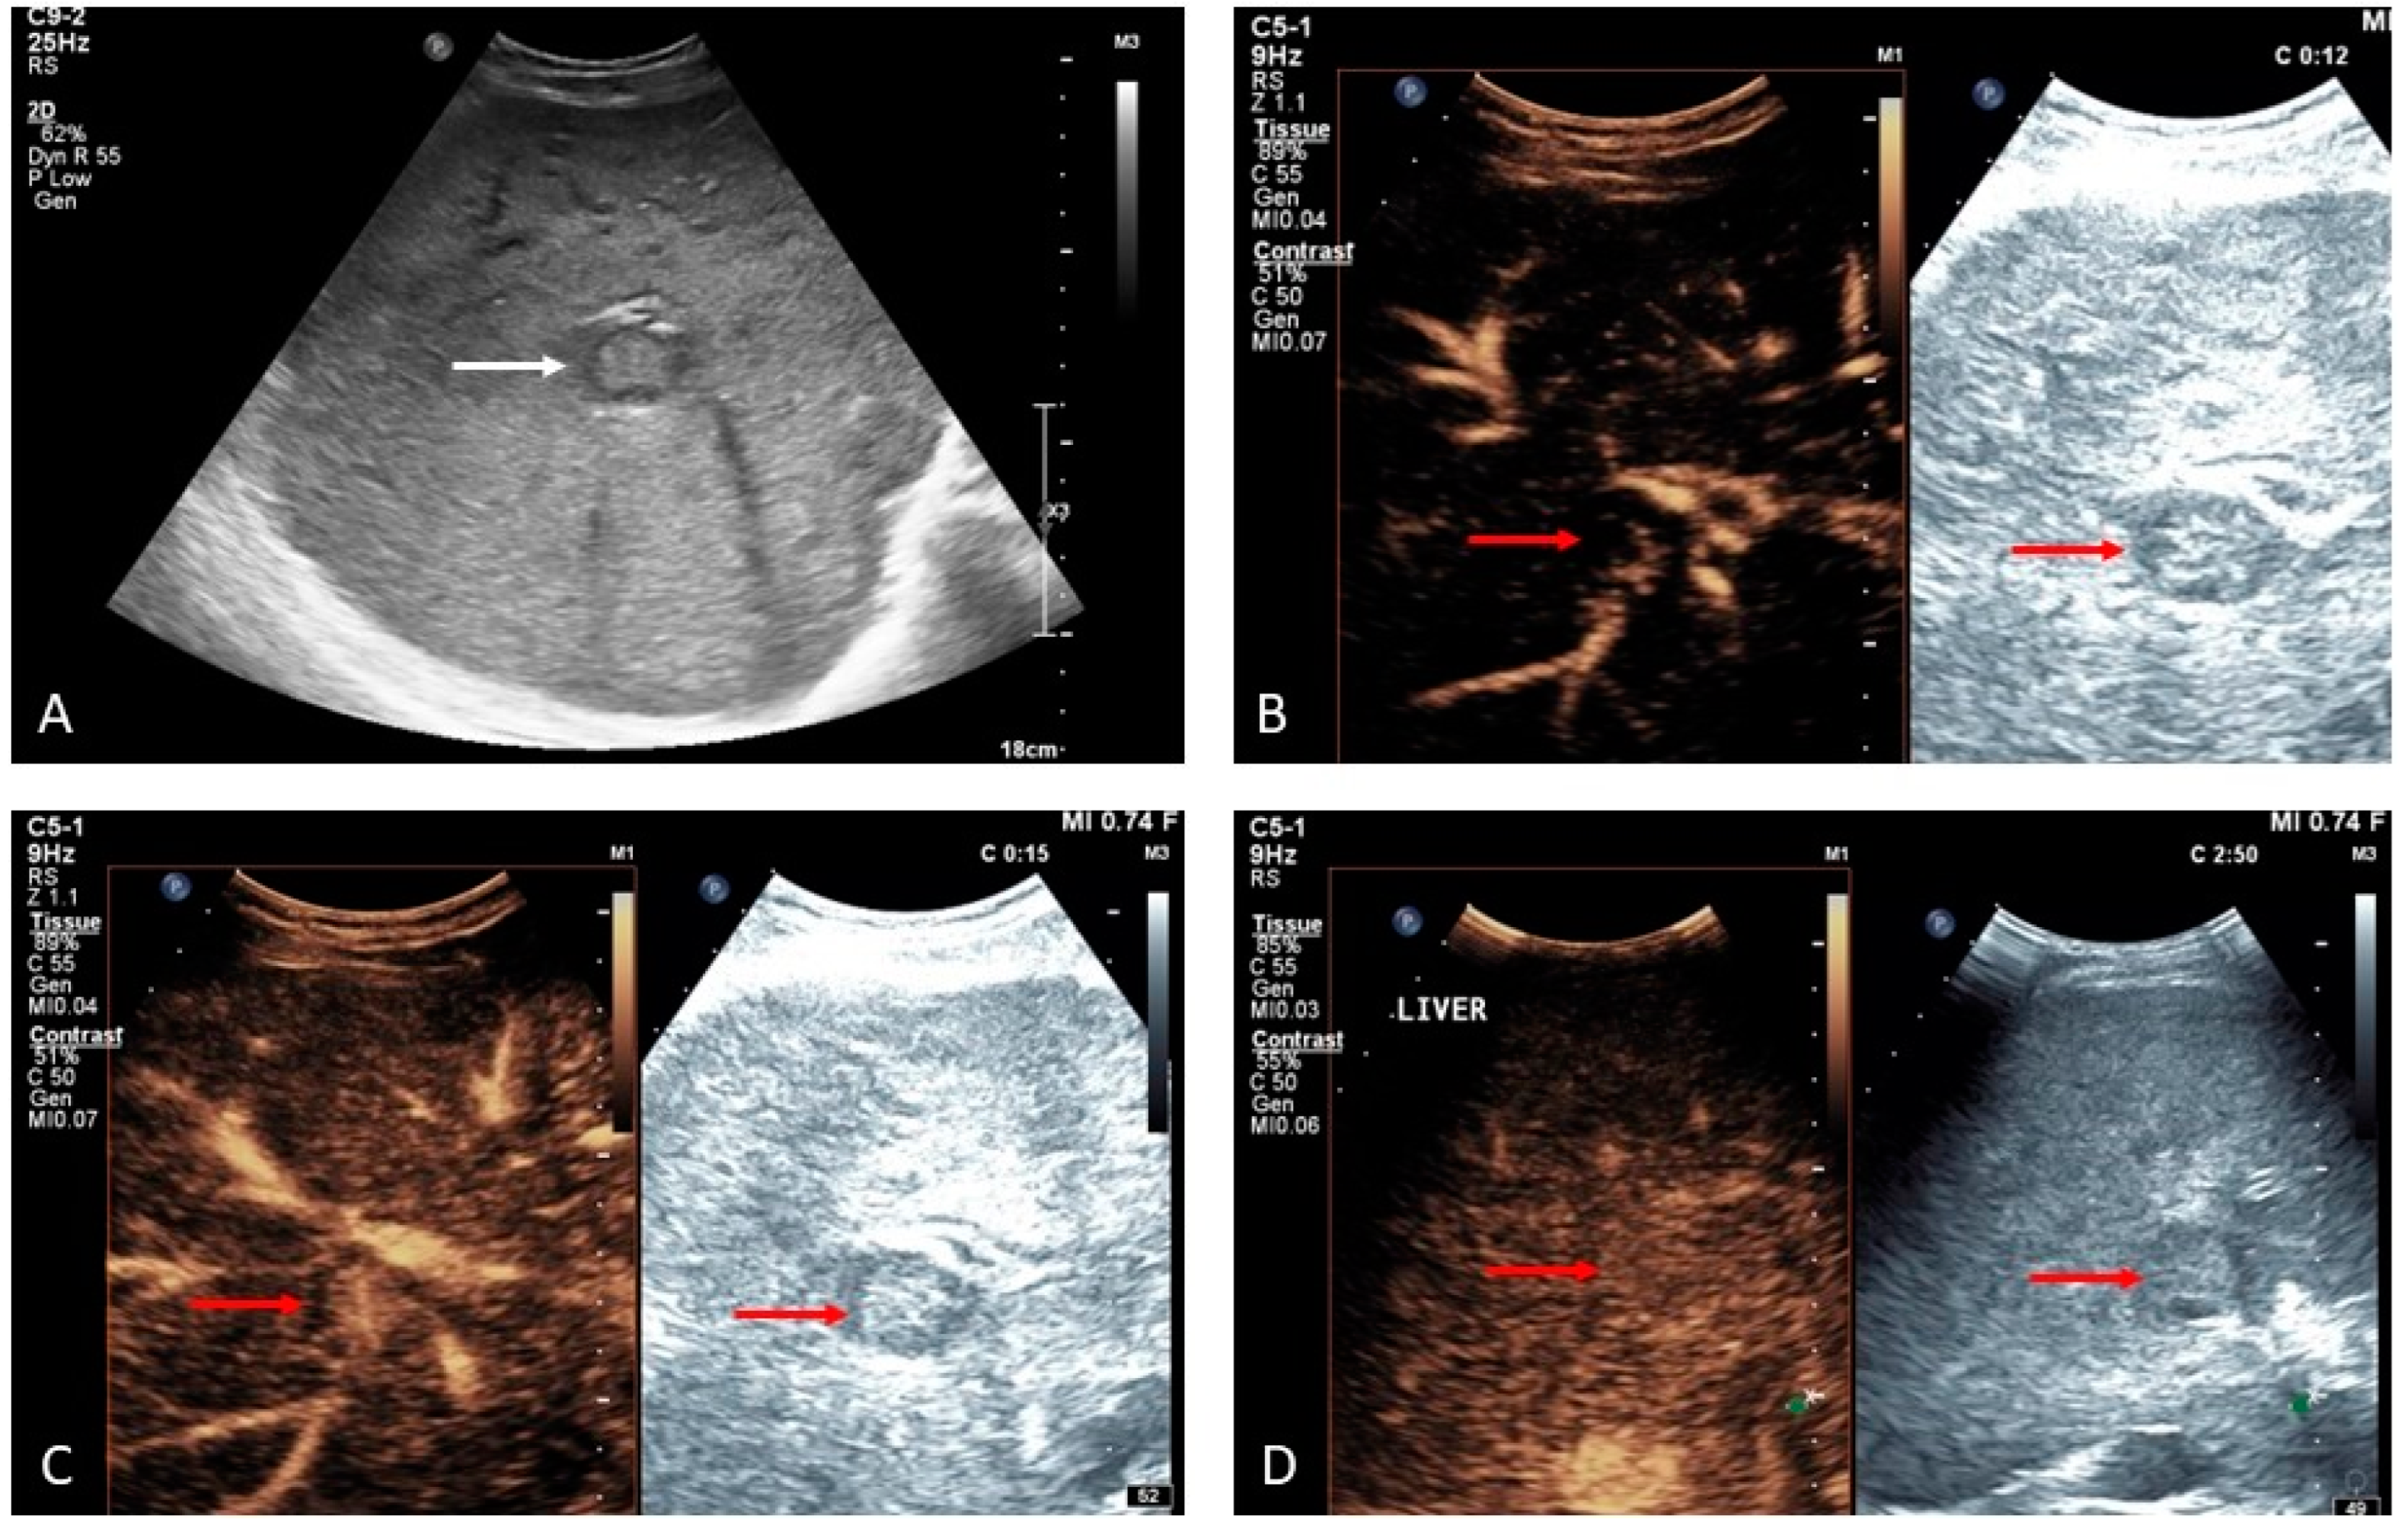

2. Portal Vein Thrombosis

- (i)

- the presence of primary or secondary liver malignancy and echogenic material filling the portal venous lumen;

- (ii)

- the diameter of the lumen of the portal vein is often increased according to the growth of the tumor within the vessel;

- (iii)

- evidence of vascularization of the thrombus as a consequence of neoplastic neoangiogenesis [1].